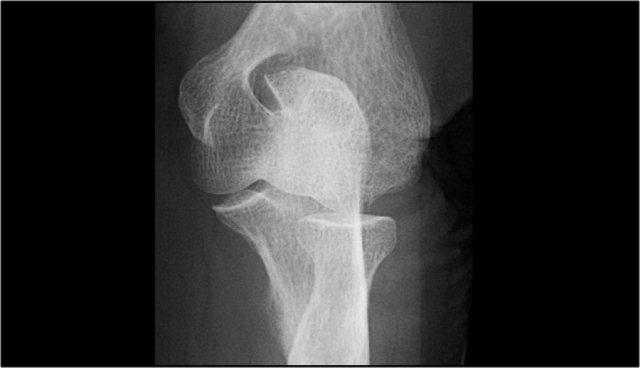

Hình chụp X-quang của một vận động viên bóng chày 15 tuổi với tiền sử đau khuỷu tay 4 năm và gần đây có triệu chứng kẹt khớp.

Có một vùng thấu quang khu trú ở chỏm con và một số mảnh vỡ.

Đây là hình ảnh điển hình của tổn thương sụn xương chỏm con và hiện tượng kẹt khớp có thể là kết quả của các dị vật trong khớp.

Continue with the MR…

MR-arthrogram xác nhận tổn thương sụn xương.

Có gadolinium nằm giữa xương cánh tay và tổn thương sụn xương, cho thấy tổn thương này không ổn định.

Nếu không có gadolinium, hãy tìm dịch khớp chui xuống dưới mảnh sụn xương.

Có một mảnh thể tự do trong ngách sau của khớp quay-cánh tay.

Notice also the fragmentation as seen on the axial image.